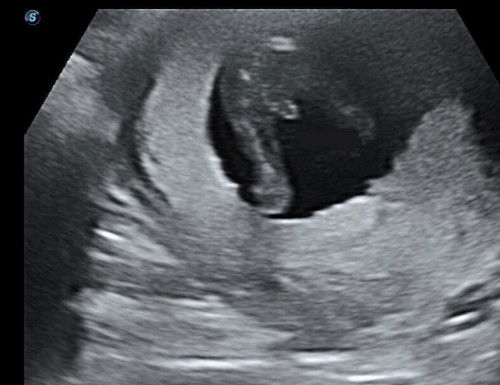

Boy or Girl? 👀

Kandungan 16 minggu. Saja je pergi utk growth scan. Pastu nampak gender skali. Doc kata ni dah macam confirm baby boy. Tapi dia kata takleh nk kata jugak sbb, semua baby akan jadi boy dalam masa 16-17 minggu. After tu baru boleh confirm and check balik boy or girl tapi dia kata ni mcm dah jelas sangat je boy tapi dia pesan jangan beli baju lagi 😂 Saja nak share sini kot orang lain ada pengalaman scan & dapat nampak gender awal2 jugak macam saya. Mommies semua nampak boy kan? Geng daddy dia lah! Mak dia nak girl senanya, tapi takpe je mana2 pun saya bersyukur boy or girl asal baby sihat walafiat sempurna anggota badan, mana2 pun okayyy.